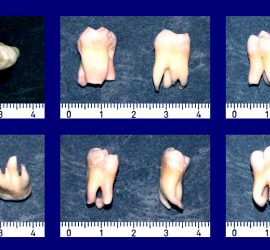

Жевательная проба. Критерий оценки эффективности работы жевательного аппарата, которую определяют по 3 показателям: жевательная эффективность, жевательный эффект и жевательная способность. Тестовым материалом для жевательной пробы могут служить пищевые продукты (орехи, морковь, хлеб) и искусственно созданные (20% желатина, отвержденная в 4% формалине, ортосил, другие пластмассы). Обязательным условием для воспроизводимости результатов пробы […]